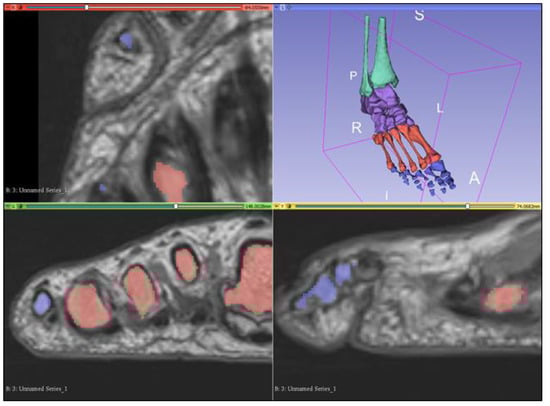

2.2. Segmentation of Bony Anatomy

2.3. Segmentation of Musculature